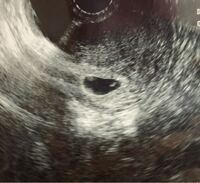

Web妊娠6週ころの超音波写真 心拍が確認できることもあります 小さな豆粒の赤ちゃん(胎芽)が細長く成長してきます。 心拍を確認できることもありますが、まだ微弱です。 超音波写真Web6w入って心拍確認できませんでした。 先生には、6週入ったら100%心拍確認できる。 次は2週間後に来て、その時どちらか確定すると言われ 不安でいっぱいです。 排卵日がずれてる可WebFHR 139bpm(112bpm) ※カッコ内は先週6W1D 胎芽の成長は1日mmと聞くから今日は10mm越えを目指していたのだけどそれはならず。 エコー写真にも6W6D相当と表示があるけれど、

妊娠6週1日 6w1d の超音波 エコー 写真

妊娠6w1dのエコー写真 ページ3